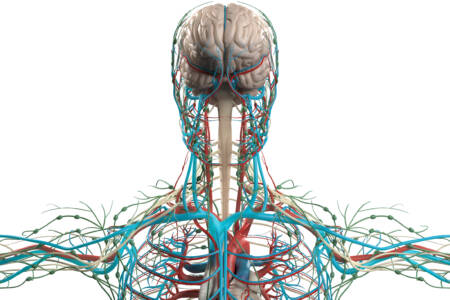

Wer Haut und Organe per Tissue Engineering herstellen möchte, benötigt körperverträgliche Mikrofasern als Gerüst. Daran forscht ein Team der TU Graz.